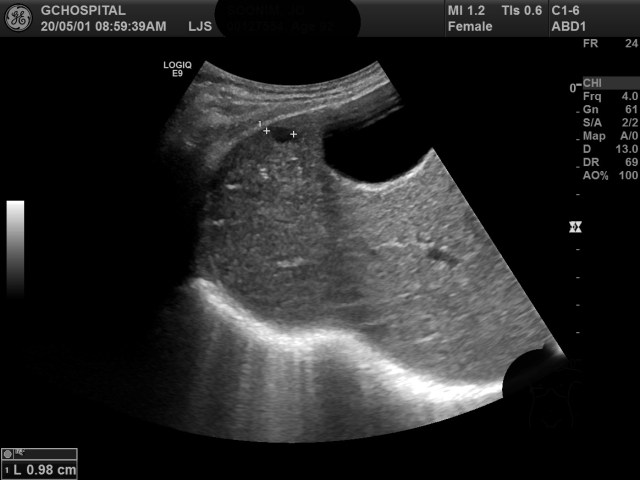

위의 영상은 앞서 두번째 영상에서 추가로 보였던 단순낭종을 늑골 사이로 접근해서 촬영한 영상입니다. 내부에 훨씬 더 뚜렷한 무에코를 확인할 수 있을 뿐 아니라, 늑골 밑으로 접근한 영상에서는 확인하는게 불가능했던 후방에코증가소견도 뚜렷하게 볼 수 있었습니다.